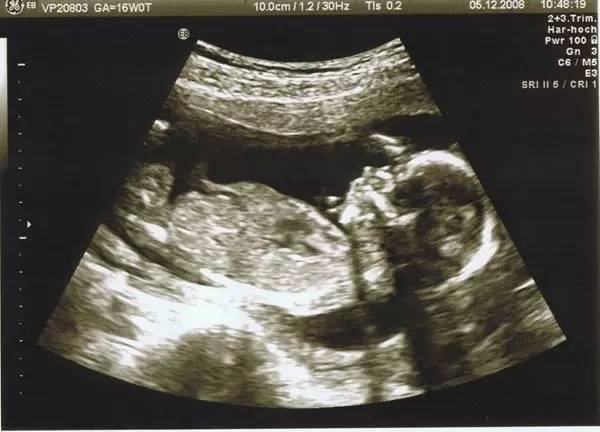

(NT超声图)

“NT”是“颈项透明层”的英文简写,是指流动在颈项后面的一层半透明蛋白膜,胎宝宝在10~13周时,可用B超来成像,通常说为B超NT。

正常胎儿的NT厚度应该在3.0mm以内。NT超过正常值,越厚,说明唐氏儿风险就越高。